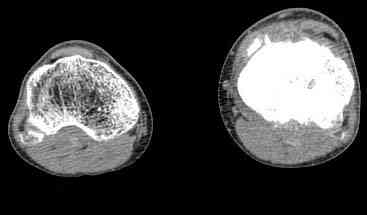

важаемые коллеги! Поступил больной 22 лет. Болен с января 2006 - появились боли в области верхнейтрети голени. При первичном осмотре в поликлинике был заподозрен первично-хронический остеомиелит - осмотрен гнойным хирургом - произведена биосия . Заключение - хондросаркома. Осмотрен онкологом - с учетом характера опухоли - химиотерапия, лучевое лечение не показано. Предложена либо ампутация, либо решение вопроса о возможности выполнения органосохраняющей операции. При обращении к нам произведена сцинтиграфия скелета - зоны гиперфиксации РФП: верхняя треть голени- 960%, нижняя треть бедра - 380%, Дистальный метафиз голени и затылочная область - 140%. В легких - метастазов нет. Произведена КТ (картинки в приложении). Учитывая абсолютную нестыковку рентгенологических и морфологических данных повторно биопсия. Выявлено, что первичная биопсия выполнялась из поверхностной параоссальной зоны - там локализованы хрящеподобные массы, далее очень плотная кость без хрящевых участков - биоптат взят фрезой с большим трудом. Морфологического заключения пока нет. Хотелось бы узнать Ваши варианты диагноза и соответственно тактику.

Не специалист по онко ортопедии, но по локализации (бедро, большеберцовая и плечевая кость), возрасть, в данный момент отсутствия метастаза и формация новой кости с мягкотканним вовлеченим, процесс больше напоминает остеосаркому большеберцовой кости.

Биопсия затрудняется из-за склероза, онко ортопеды пользуются для биопсии специальным набором режущих игл.